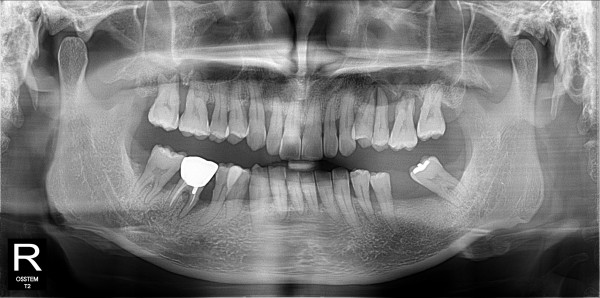

구치부 임플란트 최고관리자 0건 23-11-07 18:29 본문 구치부 임플란트 목록 이전글구치부 임플란트 23.11.07 다음글구치부 임플란트 23.11.07 댓글목록 0 댓글목록 등록된 댓글이 없습니다.